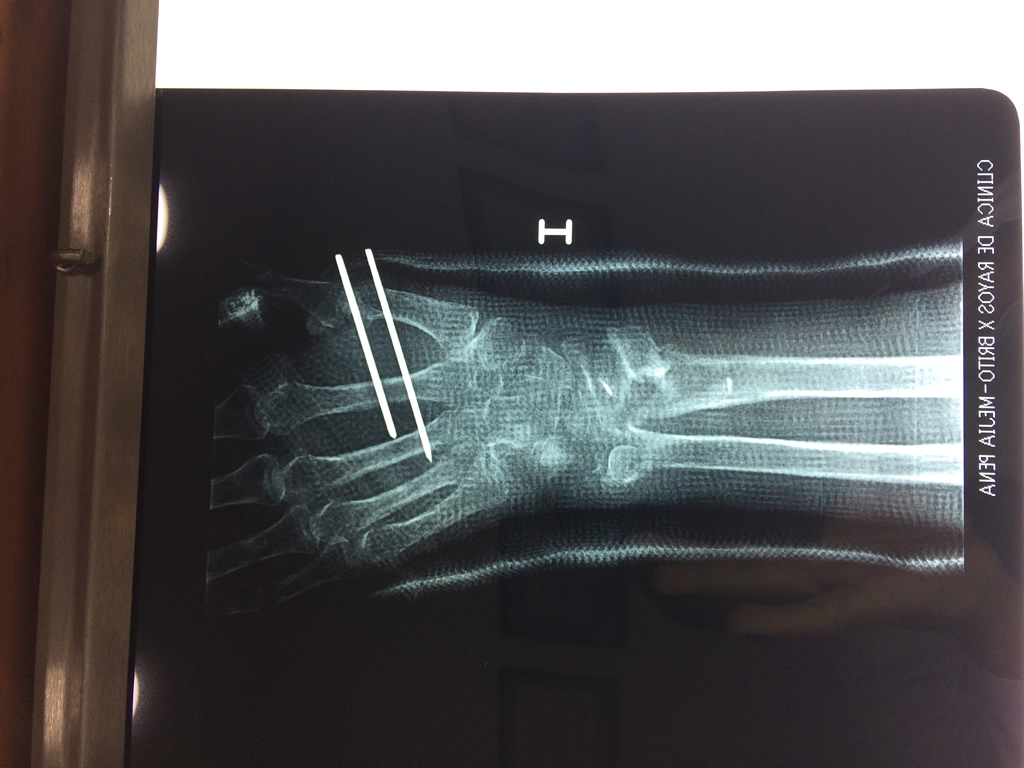

Cirugía de Muñeca y Mano

Los procedimientos más comunes en cirugía de la mano son aquellos destinados a reparar traumatismos, incluyendo lesiones de tendones, nervios, vasos sanguíneos, y articulaciones; huesos fracturados; y quemaduras, cortes, y otros daños de la piel.